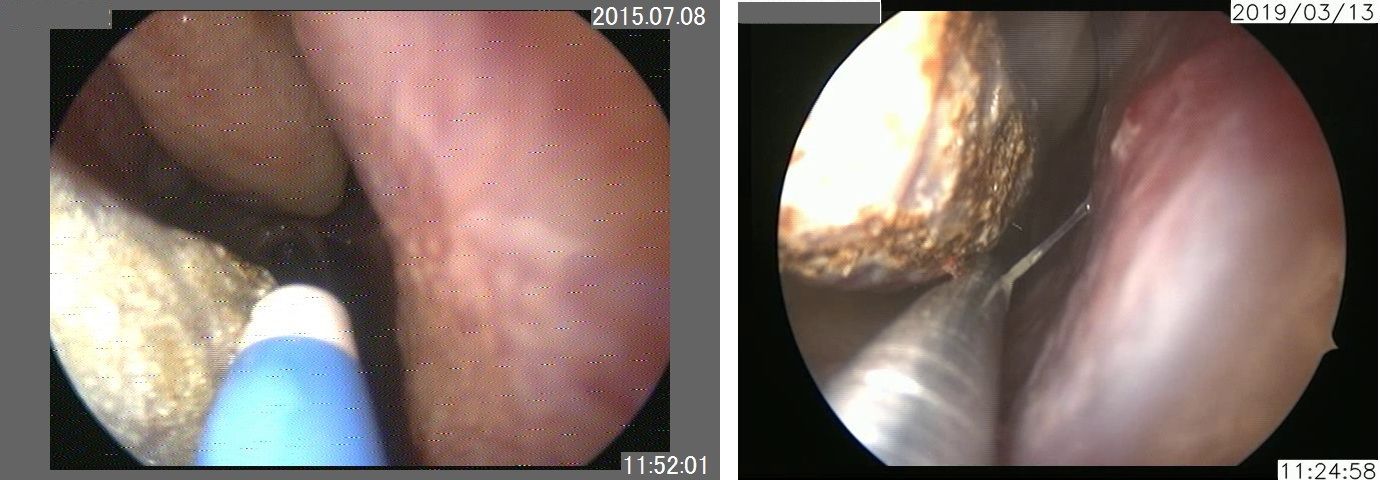

当院では内視鏡で観察しながら施行しますので、鼻腔奥の部分も明視下に焼灼することが出来ます。上左図はアルゴンプラズマ、上右図は炭酸ガスレーザーによる焼灼術中の映像です。